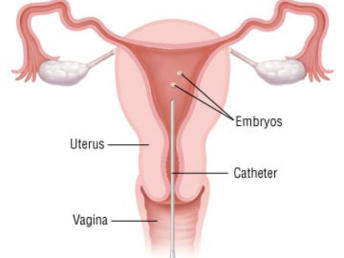

03. Male and female reproductive health care.

Expert evaluation and treatment of reproductive health concerns, ensuring safe, confidential, and holistic urological care for all patients.